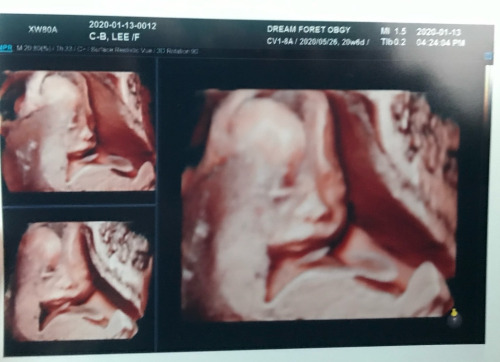

결혼식 일주일 앞둔 임신 6개월 차

석 달 정도 치료 끝에 퇴원한 나. 그러나 부모님과의 관계는 여전했고 회복불가였다. 그러다 보니 나는

이 지옥에서 벗어날 방법이라곤 결혼밖에 없단 생각을 했고, 앞서 말한 혼전임신으로 도망치듯 집에서 나왔다.